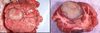

What are the molecular and morphologic changes of the image? ( MDx)

Clinical history and signs: 3 week old puppy, anorexia, dypsnea, abd pain upon palpation, normal rectal temperature

Multifocal, acute renal necrosis and hemorrhage or necrohemorrhagic nephritis

What is the etiology?

Clinical history and signs: 3 week old puppy, anorexia, dypsnea, abd pain upon palpation, normal rectal temperature

Canine herpesvirus-1 (CHV-1)

- red spots are from the virus targeting endothelium

What is the pathogenesis?

Clinical history and signs: 3 week old puppy, anorexia, dypsnea, abd pain upon palpation, normal rectal temperature

Transmission CHV-1 to pup at birth >incubation period of up to 1 week > virus replicates at temperature lower than 37C (98.6F) > endothelial cell tropism > multifocal necrosis in numerous organs